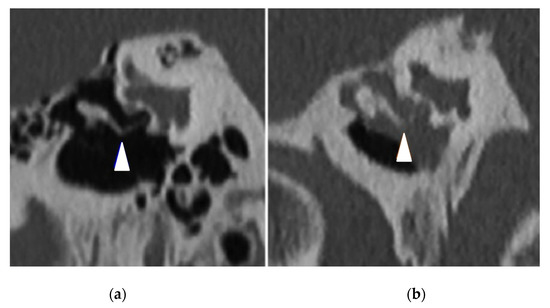

| Abnormal CT scan, | 32 (94%) | 11 (32%) | <0.0001 |

| Mastoid opacification | 13 (38%) | 8 (24%) | 0.19 |

| Mastoid condensation | 21 (62%) | 8 (24%) | 0.01 |

| Middle ear inflammation | 22 (65%) | 7 (21%) | 0.0002 |

| Ossicular anomaly | 12 (35%) | 3 (9%) | 0.01 |